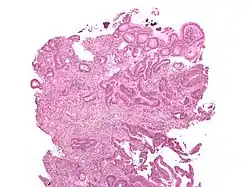

Intestinal injury

A total of 58 cases of intestinal injury including necrosis of the colon have been reported with polystyrene sulfonate as of 2013.[9] Well more cases have been reported when used in combination with sorbitol and other cases have occurred when used alone.[9]